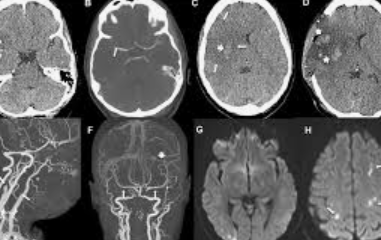

뇌졸중 전조증상을 파악하고, 조기발견의 중요성을 강조하는 가장 주목할만한 임상 시험 중 하나는 NINDS(미국 국립 신경질환 뇌졸중연구소)에서 실시한 NINDS rt-PA Stroke Trial입니다. 1995년 "The New England Journal of Medicine"에 발표된 이 연구 결과에 따르면 뇌졸중 증상이 시작된 지 3시간 이내에 혈전 용해제인 rt-PA를 투여한 환자는 치료를 받지 않은 사람들에 비해 3개월 후 장애가 거의 없거나 전혀 없었습니다.